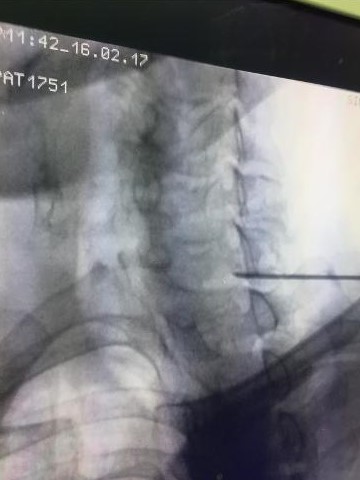

At RK Pain Management Clinic, we are dedicated to providing comprehensive, compassionate care to individuals suffering from chronic pain.